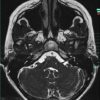

U dây VIII

» Thông tin: Nữ giới – 35 tuổi.

» Lâm sàng: Điếc đột ngột.